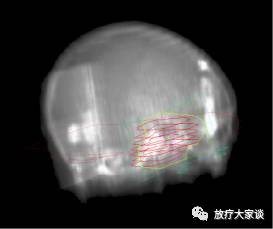

3)RT图像(RT Image)。对锥形几何条件下生成的图像的定义,如采用常规模拟定位机、接口图像设备(electronic portal image device, EPID)。也可以是按照相同的锥形几何条件计算得到的图像,如数字化重建放射图像(digitally reconstructed radiographsDRRs)。

放疗计划系统有哪些放射治疗计划系统(TPS)介绍_https://www.jmylbn.com_新闻资讯_第18张